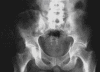

Case presentation: We describe two cases of non-traumatic acetabular and vertebrae fractures following seizures without history of epilepsy. They occurred in two male patients, 18 and 48 years old suffering respectively from hypercorticism and poorly controlled diabetes mellitus. Seizures, occurring inside hospital, were secondary to hypertensive encephalopathy crisis with hypokaliemia in the first case and severe hypoglycaemia in the second one. Fracture was promoted by a decrease in mineral bone density caused respectively by hypercorticism and diabetic chronic renal failure.